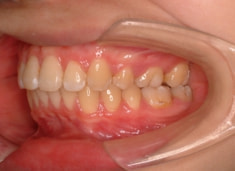

治療前